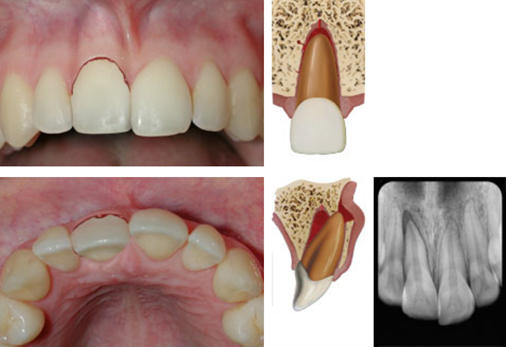

dx lateral luxation

A

Displaced usually in palatal/lingual or labial direction

High metallic/ankylotic sound

Usually mobile

Sensibility tests will likely give a lack of response except for teeth with minor displacements.

* The test is important in assessing risk of healing complications. A positive result at the initial examination indicates a reduced risk of future pulp necrosis.

Occlusal, PA and 2 eccentric exposures from diff horizontal angulations

* Widened PA ligament space